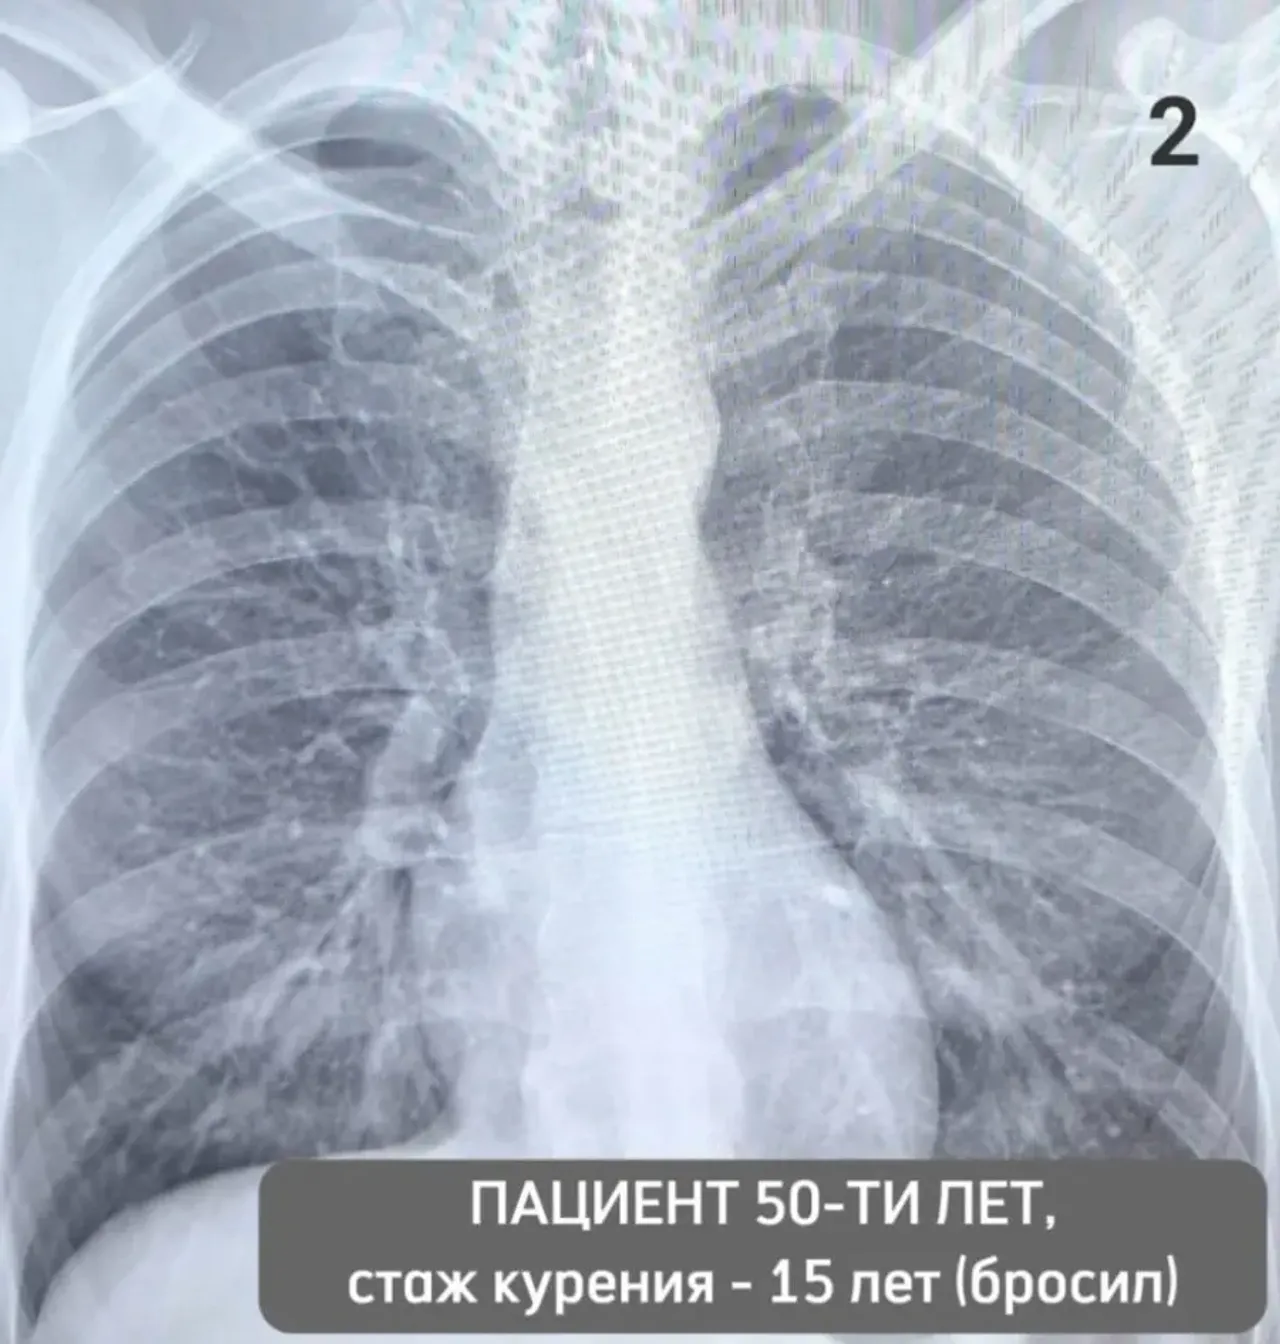

Нет то есть в легких 116 фото